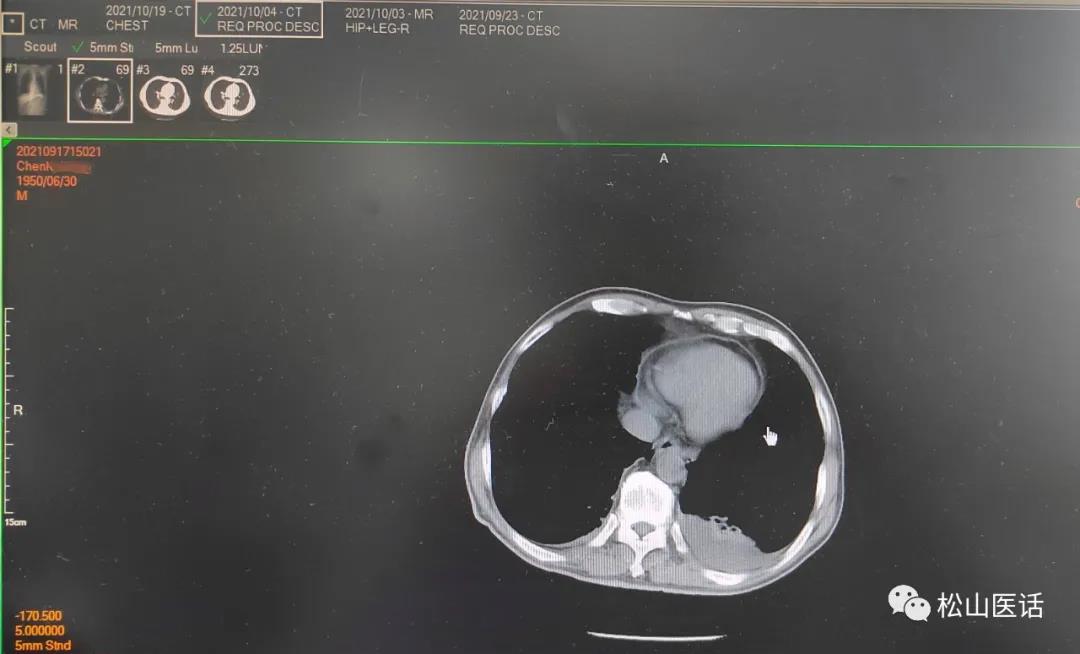

2021-10-04CT报告

难道是肺部感染加重了?肺部CT的复查结果显示:

影像对比

10月4号与9月23号比较没有明显改善,双侧胸腔少量积液但以左侧较多。

于是作出判断:骨髓的阳性细菌感染是正确的, 引起感染性高热可能性来自于肺部的胸腔少量积液,最大可能性是肺部真菌感染 ,